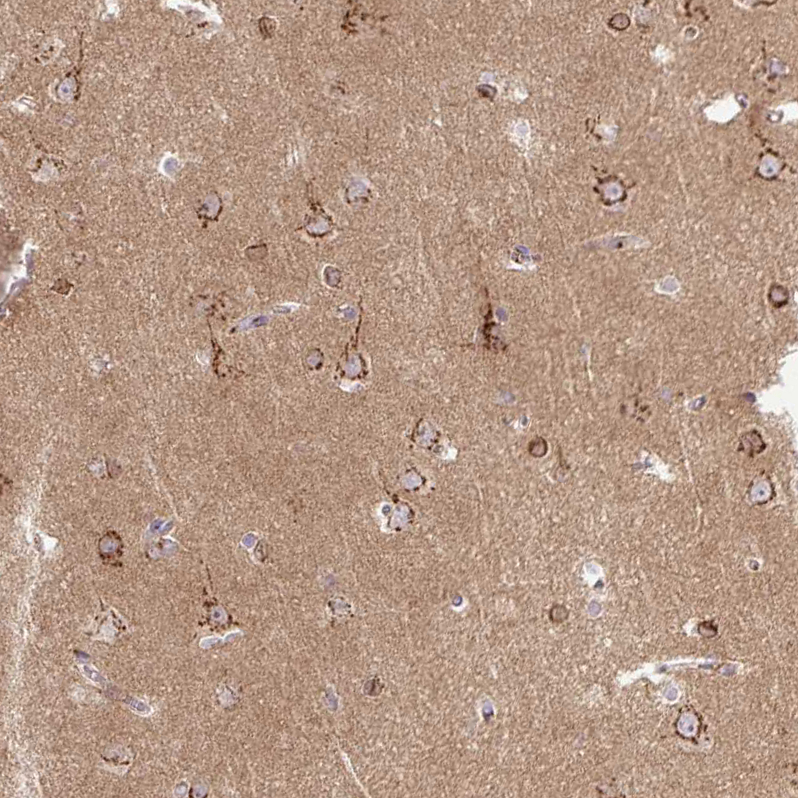

Immunohistochemical staining of human placenta shows strong cytoplasmic granular positivity in trophoblastic cells.